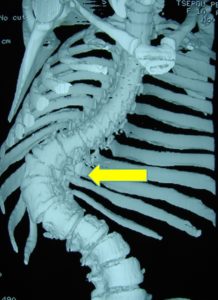

Β. Αξονική Τομογραφία Σ.Σ.: Προεγχειρητική Αξονική Τομογραφία η οποία κάλυψε όλη την έκταση από την Αυχενική Μοίρα της Σπονδυλικής Στήλης (Α.Μ.Σ.Σ.) μέχρι το ιερό οστούν

1. Μετωπιαία τομή (coronal) : Παρατηρείται ατελής σχηματισμός και διαχωρισμός των σπονδύλων σε πολλαπλά συνεχιζόμενα επίπεδα

2. Εγκάρσια Τομή (Axial) (α,β)

Παρατηρούνται :

- Μεγάλη στροφή των σπονδύλων και των σπονδυλικών σωμάτων λόγω της σκολίωσης.

- Συγγενείς ανωμαλίες-ημισπόνδυλοι.

- Πλευροσπονδυλικές ανωμαλίες, συνοστεώσεις πλευρών και σπονδύλων.

- Εξαιρετικά μικρές διαστάσεις των μίσχων των σπονδύλων (pedicles) και των σπονδυλικών σωμάτων

- Μεγάλες διαστάσεις του σπονδυλικού σωλήνα.

- α

- β

- γ

3 . Οβελιαία – πλαγία (Sagittal) τομή

Παρατηρούνται :

- Ημισπόνδυλοι.

- Ενοποίηση των σπονδύλων, των σωμάτων προσθίως και των τόξων οπισθίως σε μεγάλη έκταση.

Δεδομένου ότι αυτές οι ανωμαλίες έχουν επεκταθεί μέχρι την ανωτέρα Α.Μ.Σ.Σ., έχουν προκληθεί διαταραχές στην περιστροφή της Α.Μ.Σ.Σ. η οποία είναι πολύ περιορισμένη.